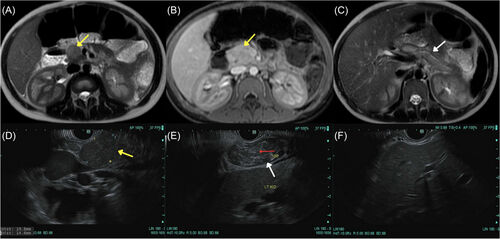

⚠️ Food impaction + normal-ish biopsy ≠ no #EoE.

Mahon et al. show 4 kids with sub-diagnostic eosinophil counts at #EFI who ALL had EoE confirmed on repeat scope. Don't let them fall through the cracks! 👇 #PedsGI #Esophagus #GITwitter